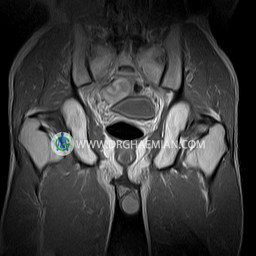

پزشکان اغلب از تصویربرداری ام آر آی برای تشخیص و درمان عارضه های پزشکی که فقط با استفاده از اشعه ایکس یا میدان مغناطیسی و امواج رادیویی قابل مشاهده است، استفاده می کنند. دستگاه ام آر آی تصاویر دقیق از ساختار های داخلی بدن ایجاد می کند. در این کیس استئومیلیت لگن، آتروز و سنیویت دیده می شود.

Technique : coronal STIR , coronal T2 , Axial T1 , axial T2 .

Each femoral shaft has normal margins and contains a normal bone marrow signal .

– Heterogeneous signal change (high T2/STIR , low T1) in proximal metaepiphysis of left femur without articular surface irregularity suggestive for bone bruise (stress fracture?), osteomyelitis & arthritis and marrow infiltration (less probable)

– Left hip joint effusion suggestive for synovitis

are seen.